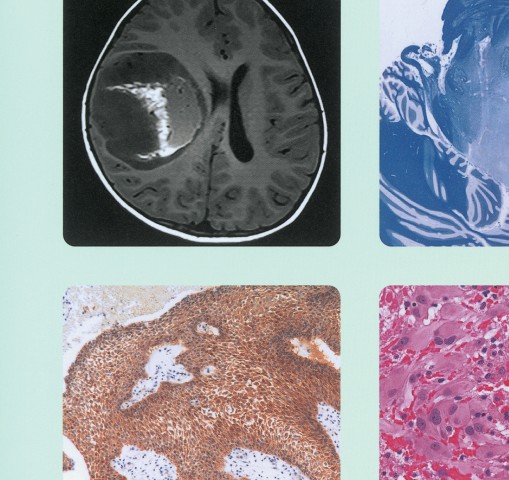

脳腫瘍病理の詳細を網羅した専門書。- タイトル: 脳腫瘍病理カラーアトラス 第4版- 内容: 脳腫瘍病理に関する詳細情報- 言語: 日本語- 出版社: 医学書院- 版: 第4版一部マーキングがあります。ページ上部に印鑑が押してあります。画像が多く、わかりやすい専門書だと思います。状態としては比較的綺麗かと思いますが、神経質な方はご遠慮ください。ご覧いただきありがとうございます。